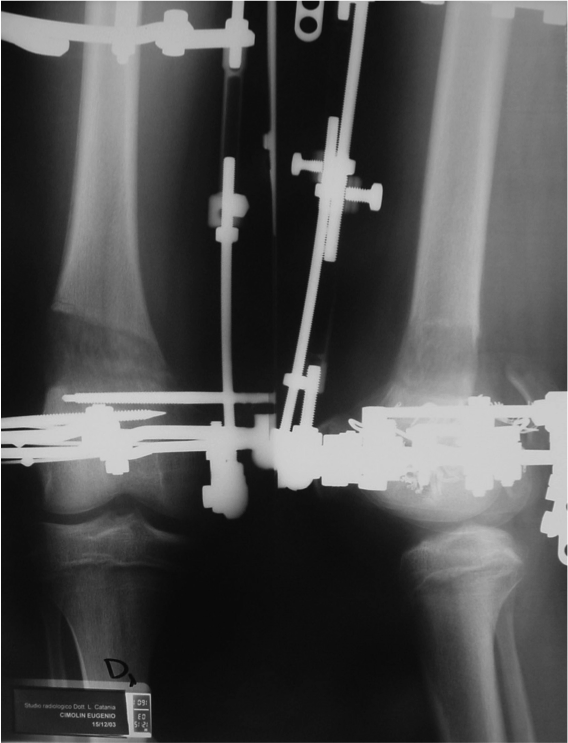

Correzione della deformità in valgo con ipercorrezione in varo